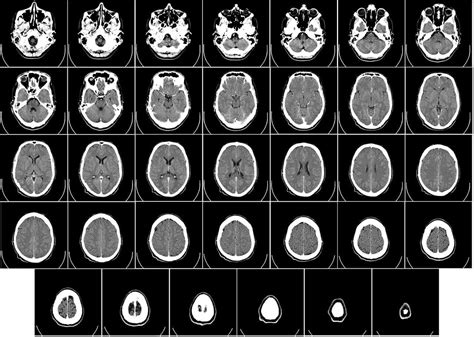

Zobrazovacie metódy

Zobrazovanie mozgu pomocou CT alebo MRI sa nevykonáva rutinne pri každom otrase mozgu. Tieto vyšetrenia sa indikujú pri prítomnosti varovných príznakov, ako sú pretrvávajúce vracanie, zhoršujúca sa bolesť hlavy, opakované bezvedomie, kŕče, fokálne neurologické príznaky alebo podozrenie na fraktúru lebky.